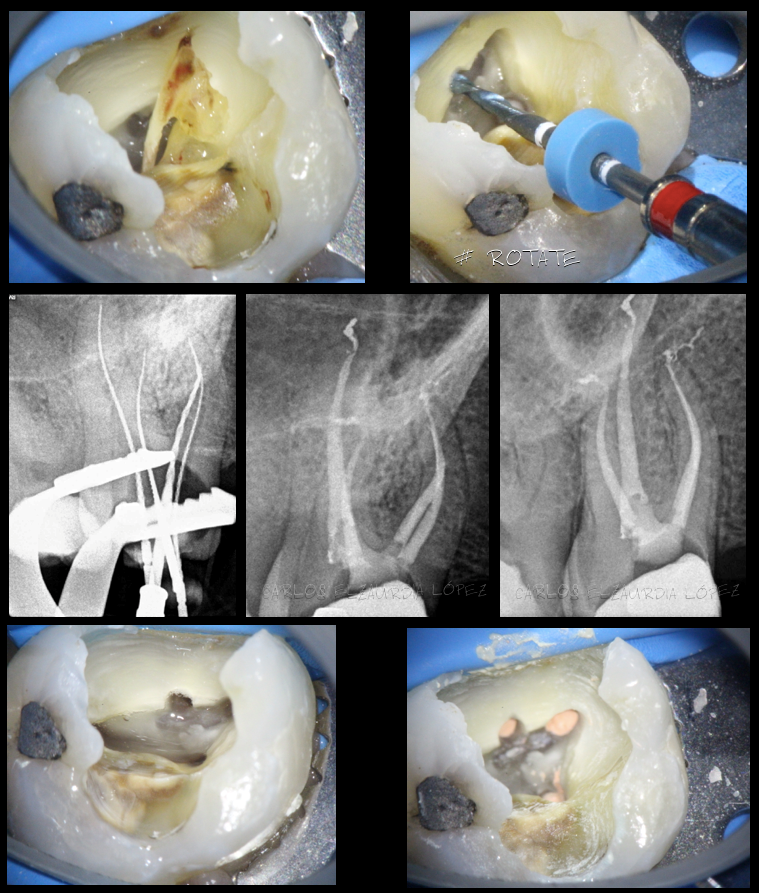

NECROPULPECTOMIA 4.6

Tratamiento de conductos en una pieza necrotica. Cabe destacar la importancia de la irrigación y de la activación en este tipo de tratamientos, para conseguir permeabilidad apical y posterior sellado tridimensional Restauración mediante incrustacion con protección cúspidea de Enamic. Evolucion del caso al año, con el paciente asintomático. Caso2. BIOPULPECTOMIA 1.6 Eliminación de un pulpolito […]